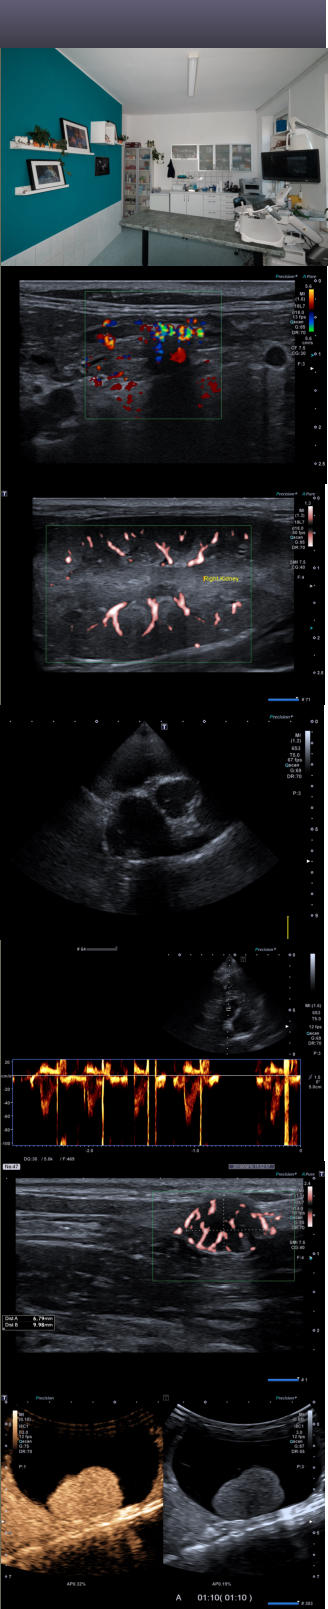

Unsere   Praxis   verfügt   über   2   Ultraschallgeräte:   Das   SonositeM- Turbo    ist    ein    transportables    Ultraschallgerät,    welches    eine    für seine   Größe   hervorragende   Bildqualität   liefert   und   ausgesprochen robust   ist.   Nicht   umsonst   wird   es   vom   US-Militär   und   von   der Organisation    Ärzte    ohne    Grenzen    genutzt.    Uns    dient    es    bei Hausbesuchen   dazu,   einen   Ersteindruck   zu   gewinnen   und   gleich vor Ort nötige Maßnahmen ergreifen zu können. Für    weiterführende    Untersuchungen    steht    uns    mit    dem    Canon Aplio    i-800    in    der    Praxis    ein    absolutes    High-End-Gerät    zur Verfügung.     Es     verfügt     wohl     im     Moment     über     das     beste Grauwertbild    im    Ultraschall    und    dieses    ist    nach    wie    vor    die Grundlage   für   alle   weiteren   Schallverfahren,   erlaubt   es   doch   die Feststellung    von    lokalen    und    diffusen    Veränderungen    in    den parenchymatosen   Organen   oder   die   Suche   nach   Fremdkörpern   in Darm.     Unsere     umfangreiche     Sondenauswahl     erlaubt     mir, hervorragende    Bilder    sowohl    vom    Chihuahua    als    auch    vom Labrador zu machen. Neben   dem   normalen   Farbdoppler   steht   noch   der   smi-Doppler   zur   Verfügung,   welcher   noch   sensitiver   für   langsame   Blutflüsse ist   und   gleichzeitig   Bewegungsartefakte   besser   unterdrückt.   Der Spektraldoppler     ist     aus     der     Herzsonographie     nicht     mehr wegzudenken      und      erlaubt      es      Fließgeschwindigkeiten      zu bestimmen.    Der    Kontrastmittelultraschall    mittels    SonoVue oder   Luminity   ermöglicht   in   der   Leber   die   Diagnose   einer   FNH, eines    Hämangioms,    eines    Leberzelladenoms    oder    von    lokalen Leberverfettungsstörungen,       generell       eine       Unterscheidung zwischen   gut-   und   bösartigen   Veränderungen,   hilft   aber   auch   bei der   Einschätzung   von   Veränderungen   in   der   Milz,   den   Nieren   und des    Pankreas.    Und    dort,    wo    das    Bild    alleine    nicht    ausreicht, erlauben      die      Punktionsaufsätze      eine      Ultraschall-geführte Gewebsprobenentnahme   entweder   für   die   Zytologie   oder   für   die Histologie.   Auch    therapeutische    Punktionen/Drainagen    bzw. Ablationen mit Ethanol sind  möglich. Der     Ultraschall     ist     in     meinen     Augen     heute     die     beste Untersuchungsmethode    im    Bauchraum    und    ist    bei    vielen Fragestellungen   sogar   dem   MRT   bzw.   dem   CT   überlegen,   da das Auflösungsvermögen höher ist. Die   Sonographie   der   Herzens   (Echokardiographie)   gibt   mir die      Möglichkeit,      die      wichtigsten      Herzerkrankungen      zu diagnostizieren     und     einen     Therapieplan     zu     erstellen.     Der komplette   Untersuchungsgang   am   Herzen   erfordert   eine   rechts- und     linksseitige     Anschallung     des     Herzens,     um     auch     die notwendigen Doppleruntersuchungen durchführen zu können. Weiterführende   Ultraschalluntersuchungen   führen   wir   täglich zwischen       12.00       und       16.00       Uhr        durch.       Einfache Untersuchungen    einzelner   Organe   wie   z.B.   der   Harnplase,   der Prostata    oder    von    Umfangsvermehrungen    (Abdomen,    Haut), deren   Notwendigkeit   sich   in   der   Sprechstunde   herausgestellt   hat, führe   ich   in Abhängigkeit   des   Patientenaufkommens   i.d.R.      sofort   aus. Die     Kleintierpraxis     Lützschena     verfügt     mit     dem     mobilen Röntgengerät        Gamma        Vision        über        ein        modernes Hochfrequenzröntgengerät.   Der   kleine   Fokus   von   nur   1,2   mm² erlaubt       scharfe       und       kontrastreiche       Aufnahmen.       Die Röntgenaufnahmen    werden    unmittelbar    maschinell    entwickelt, was   zeitsparend   ist   und   eine   konstant   gute   Entwicklungsqualität garantiert.   Auf   eine   Umstellung   auf   digitales   Röntgen   habe   ich bewußt   verzichtet,   da   es   diagnostisch   kaum   Vorteile   bietet   und nur das Aufnahmemedium ein anderes ist. Im    Normalfall    werden    die    Tiere    zum    Röntgen    sediert.    Dies erlaubt    einerseits    ein    bessere    Lagerung    des    Tieres    für    die Röntgenaufnahme,    was    unabdingbar    ist    für    ein    aussagefähiges Röntgenbild,     und     andererseits     ist     dies     gegeben     durch     den Strahlenschutz,       da       möglichst       niemand       innerhalb       des Kontrollbereiches am Röntgentisch zu stehen hat. Röntgen      ist      das      Untersuchungsmedium      der      Wahl      bei Erkrankungen       des       Bewegungsapparates       und       oft       sind Untersuchungen   auf   HD   oder   ED   schon   im   jungen Alter   von   den Zuchtverbänden vorgeschrieben.